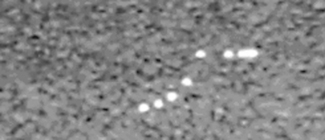

The system’s axial and lateral resolution are determined by identifying the set of two resolvable wires with the smallest separation. Figure 13.7 shows an image of a test phantom with such an arrangement of wires. It can be seen that the ultrasound system is able to resolve all targets along the vertical axis (axial plane) but is unable to resolve targets separated by a distance less than 2.5 mm across the image (lateral plane).

image

Fig. 13.7 An image of a test phantom assessing axial and lateral resolution at a specific depth